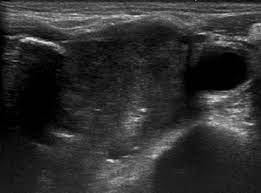

Ultrasound is often one of the first line tests in the detection of cancer. Keep in mind, however, that an ultrasound alone cannot make the diagnosis of cancer. Ultrasounds can produce false positives. Thyroid nodules are lumps that can appear in the thyroid gland in front of the throat. They increase with age and, in fact, if you look with sensitive measures like ultrasound, over 50% of people will have thyroid nodules by the age of 50 or 60. This test will usually help determine that the nodule has a low chance of being cancerous (has characteristics of a benign nodule), or that it has some characteristics of a cancerous nodule, and therefore a biopsy is indicated. Ultrasounds are not useful for treatment monitoring. While it can't diagnose cancer, it can detect the abnormal tissues that may possibly be cancerous. A small transducer (probe) both transmits sound waves into the body and records the waves that echo back. My 3.8 year old's neck ultrasound shows chain of lymph nodes bilaterally with largest on right 14mm by 6mm and largest on left 13mm by 6mm,the left one is there since a year.few intraparotid largest 5mm.thyroid & both submandibular normal. Staging head and neck cancers The most common symptom of thyroid cancer is a hard lump on the neck—but most patients experience no symptoms at all. Doctors often use them to guide a needle during a biopsy.

Ultrasound imaging can help determine the composition of lump, distinguishing between a cyst and a tumour. The survival rate in this type of cancer can be as high as 90 percent provided it is detected early in stage i itself. Throat cancer can develop in any part of the throat. The ultrasound can help to show whether a cyst has any solid areas as it is more likely to be cancer. Two in three cases of thyroid cancer occur in people under age 55, and 75%.

While it can't diagnose cancer, it can detect the abnormal tissues that may possibly be cancerous. The cells are then looked at closely in the lab. Staging head and neck cancers An ultrasound may show your doctor if a lump is filled with fluid or if it's solid. If the cancer cells look like they might have come from the larynx or hypopharynx, an endoscopic exam and biopsy of these areas will be needed. When the thyroid becomes damaged, it stops producing thyroid hormone (hypothyroidism). Throat cancer can develop in any part of the throat. Ultrasound imaging can help determine the composition of lump, distinguishing between a cyst and a tumour. And if this isn't cancer, could anybody offer an explanation as to what would cause a sore throat and growing lump? It can detect abnormal tissues, growths, and cysts and give a suspicion of cancer based on how those images look. What does ovarian cancer look like on an ultrasound is not an easy question to answer. Some symptoms of throat cancer are specific to certain areas of the body. Effective treatment is possible in many cases.